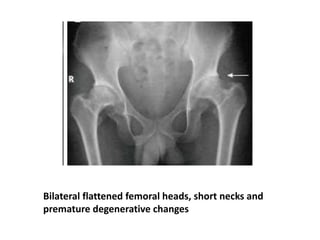

Bilateral flattened femoral heads, short necks and

premature degenerative changes

Spondyloepiphyseal Dysplasia Tarda •Later age at diagnosis and milder features(clinical attention when the child is approximately 4 years old, at the earliest) • Autosomal recessive or X-linked recessive • The spine and only the larger joints are affected. • Height is affected only minimally • Adult height may be 152 cm or more • Armspan is significantly longer than height

• 73.

• The conditionmay be first diagnosed as bilateral Perthes syndrome • SED involvement is symmetric, whereas in bilateral Legg-Calvé-Perthes disease involvement is discordant, with one hip more radiographically affected than the other • Coxa magna